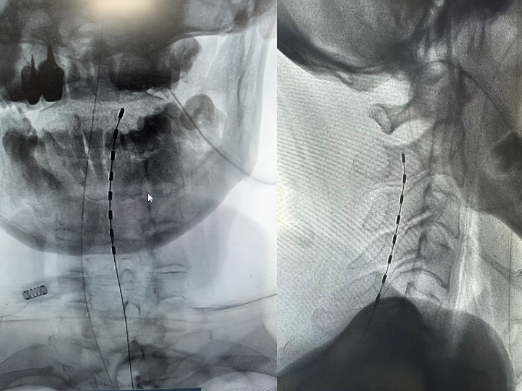

今日在祝源主任、孟亮主任的带领下,光谷神经外科团队再次成功完成一例 脊髓电刺激(SCS)穿刺电极植入手术。

与患者家属沟通后,功能团队决定对患者实施目前较为先进的脊髓电刺手术。家属也通过了解,对该手术充满信心,我科对该手术有较为丰富的经验。在多学科协作下,手术团队将电极精准植入预定位置。术中测试右侧肢体明显肌肉收缩。这为患者苏醒带来了新的希望,同时也能一定程度改善患者的肌力。希望患者早日回归正常社会生活。